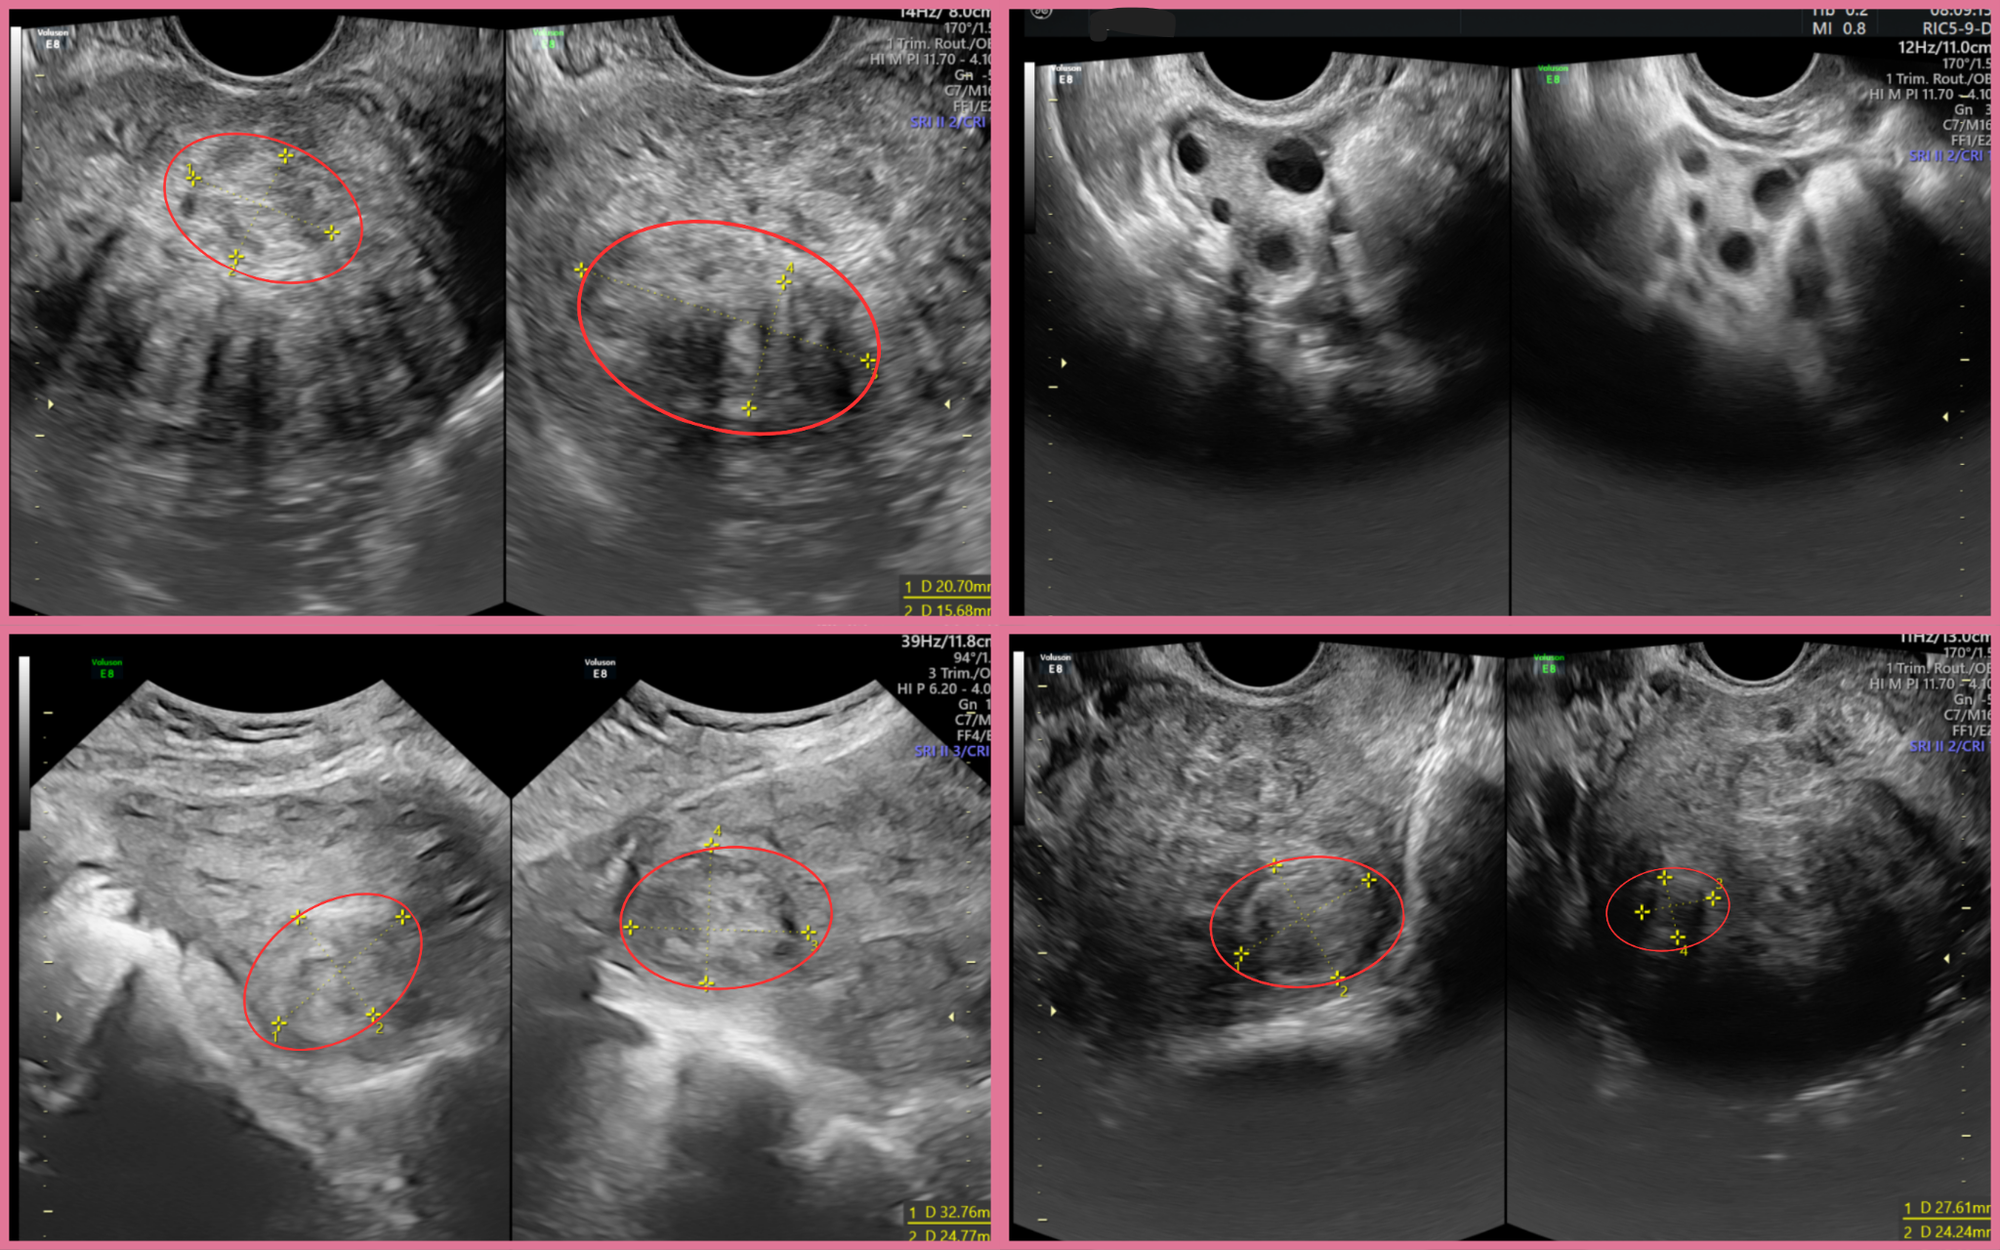

Qua thăm khám tại BVĐK Hồng Ngọc Phúc Trường Minh, các bác sĩ phát hiện tử cung của chị A có kích thước như đang mang thai 3 tháng với nhiều nhân xơ rải rác, khối lớn nhất ở thành trước kích thước hơn 4cm. Hình ảnh siêu âm cho thấy có nhiều u xơ nằm sâu trong cơ tử cung, có những khối có cuống dài và làm tử cung biến dạng hoàn toàn.

Thành tử cung biến dạng do đa u xơ.

Dựa trên hình ảnh siêu âm và kết quả thăm khám, bác sĩ nhận định các nhân xơ của chị A bám sâu trong lớp cơ tử cung, nhiều khối nằm sát nhau hoặc đan xen ở các vị trí phức tạp. Đây là dạng u xơ đa ổ khó can thiệp bằng nội soi vì nguy cơ bỏ sót u và tổn thương thành tử cung cao. Vì vậy, ê-kíp quyết định thực hiện phẫu thuật mở để có trường quan rộng, dễ kiểm soát và lấy sạch toàn bộ u.